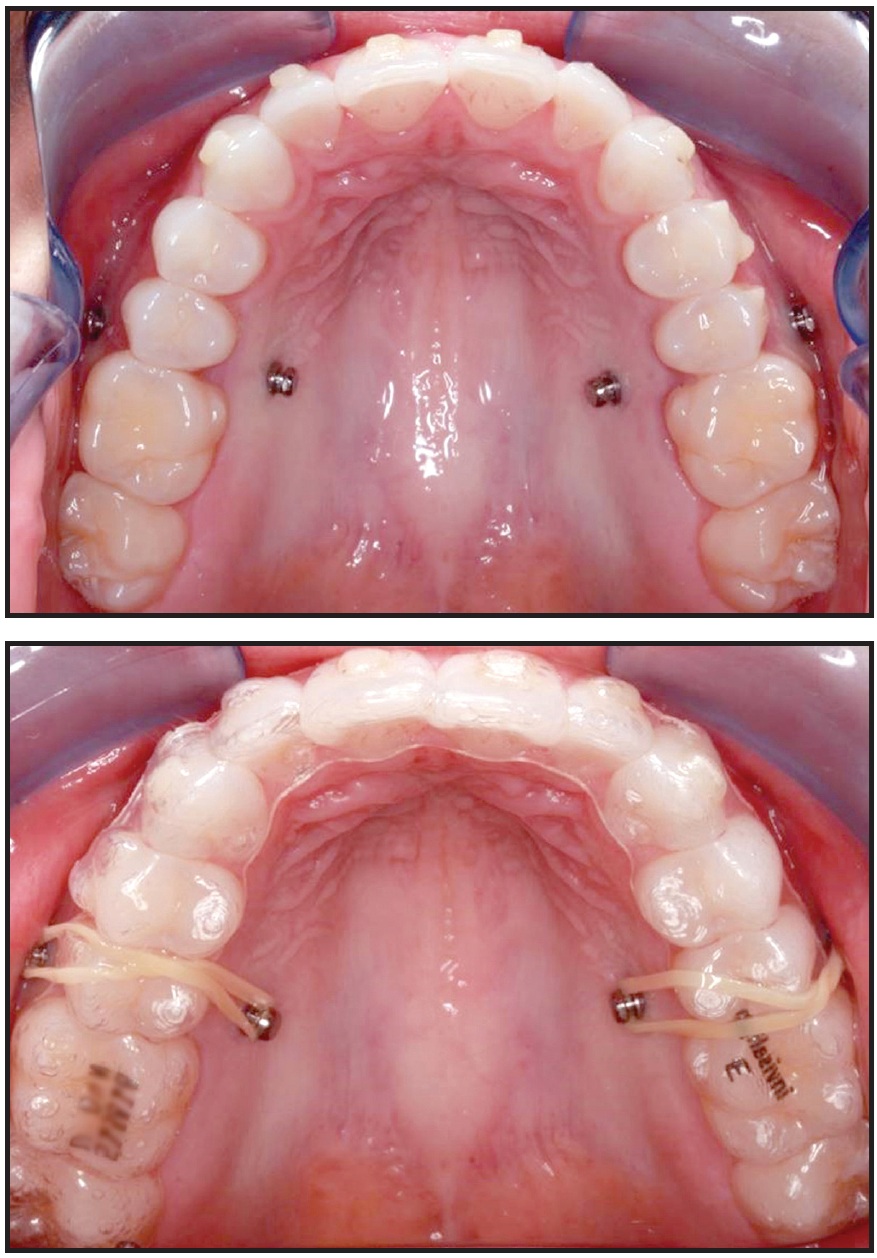

Clinicians can also take advantage of auxiliaries, such as miniscrews and bondable buttons, during clear aligner treatment. The use of miniscrew anchorage to extrude impacted upper canines or for intrusion11 (Fig. 10) is a common example.

Fig. 10 Miniscrews used with clear aligners for posterior intrusion (photos courtesy of Dr. Harry L. Dougherty Jr.).